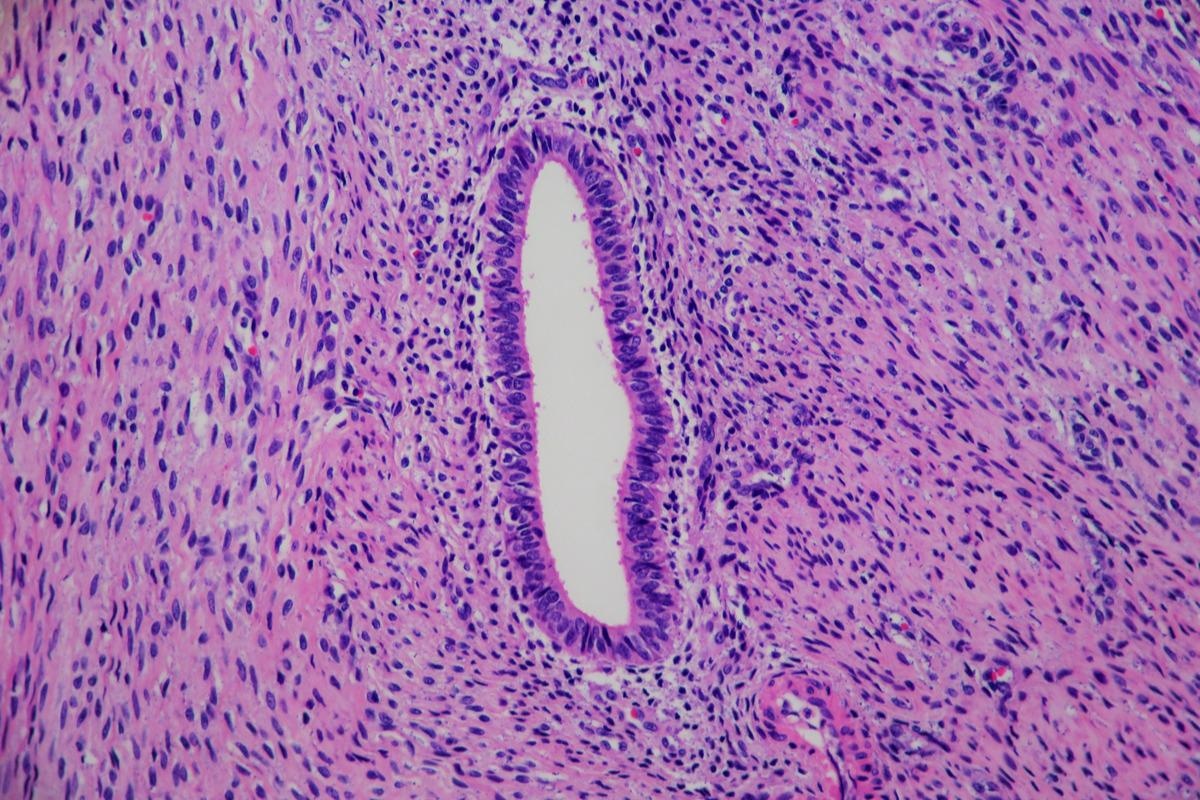

Adenomyosis is a condition that affects the uterus and is histologically characterized by ectopic endometrial glands and stroma located in the myometrial, which are surrounded by hypertrophic (a lodgement caused by the increase in the size of cells) and hyperplastic (enlargement caused by an increase in cell proliferation)  myometrial changes. The myometrium is the middle layer of the uterine wall, which is comprised of smooth muscle cells and controls the contraction of the uterus.

Image Credit: Lisa Culton/Shutterstock

Adenomyosis of the uterus. Image Credit: Lisa Culton/Shutterstock